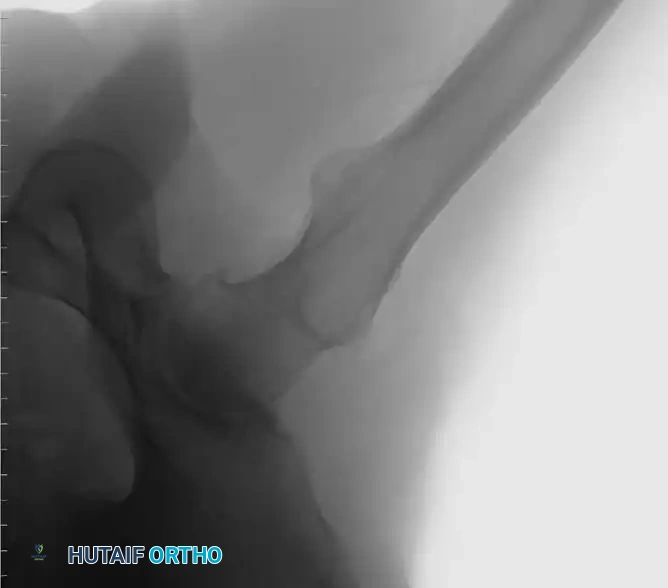

Associated Surgical & Radiographic Imaging

Hutaifortho's Orthopaedic Diagram